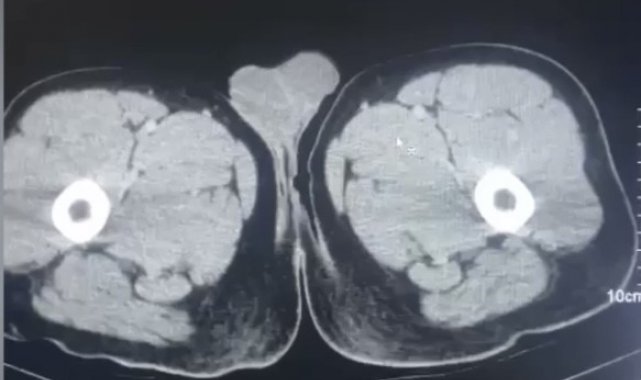

Kayseri İl Emniyet Müdürlüğü Narkotik Suçlarla Mücadele Şube Müdürlüğü ekipleri tarafından yurtdışından Kayseri'ye uyuşturucu madde getiren şahısların yakalanmasına yönelik operasyon başlatıldı. Yapılan operasyonda, yabancı uyruklu R.M.B. (29), S.N.A. (28) ve R.Y.A. (27) yakalandı. Şahısların Kayseri Şehir Hastanesi'nde yapılan muayenesinde uyuşturucu madde kapsülleri yuttukları tespit edilerek tıbbi yollarla çıkarıldı. Şahısların midesinde 17 parça halinde 212.8 gram narkotik madde ele geçirildi.

Midelerinden uyuşturucu kapsüller çıktı